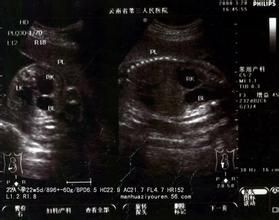

胎兒腎積水正常胎兒腎臟的集合系統可有輕度分離,分離徑可達6毫米,而胎齡大於30周后腎盂擴張≥10毫米或存在腎小盞擴張則為腎積水。腎積水分為兩種。一種為可復性:積水寬度1.01—1.63厘米之間,腎實質較厚,1.02—0.58厘米之間,胎兒出生後環境變化,積水隨之消失。常見於胎兒的膀胱內大量尿液充盈或某種原因引起的輸尿管收縮節律失調。另外部分病例的輸尿管可能存在某些解剖結構的異常。另一種為不可復性:積水寬度2.15—2.56厘米,腎實質厚0.3—0.2厘米,常見於先天性輸尿管狹窄,多有分泌功能的變化,出生後應及時治療。

綜上所述,全面了解胎兒腎積水的轉歸,定期隨訪尤為重要。如胎兒腎積水寬度0.58厘米,可視為正常;如積水寬度>2.15厘米或腎實質厚度<0.2厘米為不可復性,可視情況終止妊娠。